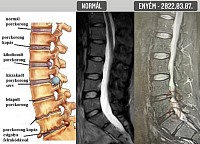

Arra már nem igazán emlékszem hogyan jutottam el otthonról a székesfehérvári MR vizsgálatra. Jó, kocsival. Oké, még vezettem is. De egy örökkévalóság volt valahogy behajtogatni magam a vezetőülésbe, Buksi szerencsére segített. Egész gyorsan megjött a vizsgálat után az orvosi vélemény. Már első blikkre láttam, hogy ehhez kevés lesz a kéttucatnyi szóból álló latin nyelvtudásom. Google, pötyögjük be. Menni fog ez. Különben is, az első mondatból a lumbalis szót még fordítás nélkül is értem. Persze úgy könnyű, hogy magyarul is ugyanúgy van. De a rohadt fájdalom mellé kell egy kis sikerélmény. Tehát gerincferdülés, meszesedés, porckorongsorvadás, eddig semmi komoly, de a harmadik mondat „adja magát”, fordítani sem kell: „Hernia disci intervertebralis foraminalis LIV-V I.s., bal L4 gyöki compresszióval, tünetképző, idegsebészeti konzílium javasolt”. Aha, orvosi szaknyelven tehát a tünetképző jelenti azt, hogy beszarsz a fájdalomtól. „17x10 mm-es extrusio látható, a bal L4 gyököt comprimálja.” Hogy dögölne meg, miért pont engem komprimál?

A hab a tortán, hogy a négyes-ötös csigolya közötti kiszakadt sérv alatt van egy „előboltosult” rész is. Szuper, legalább lesz, ami pár év múlva majd ki tud szakadni. Éljen a húszévnyi ülőmunka!